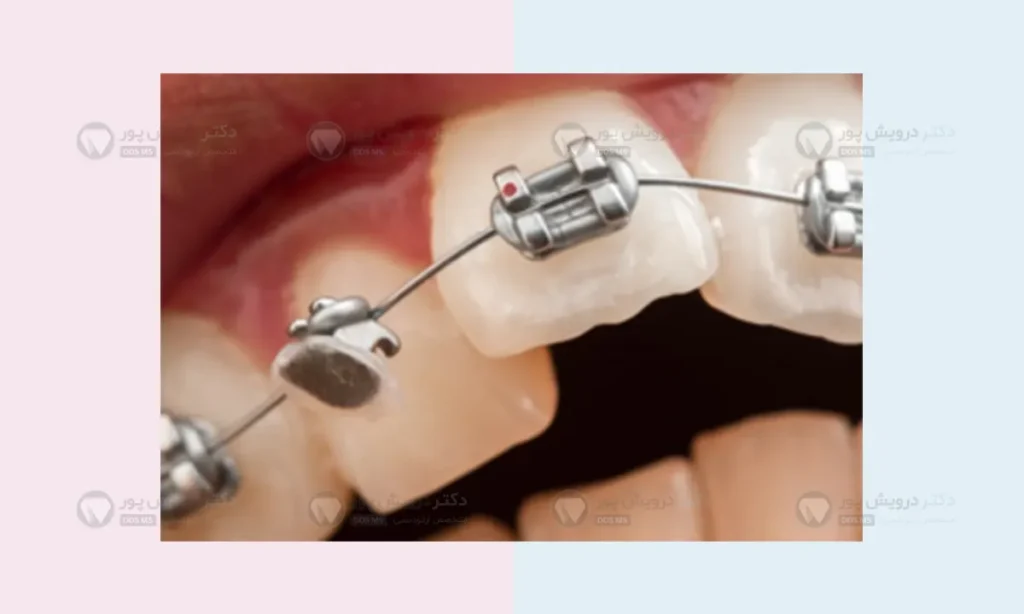

همانطور که می دانید ما در طول ارتودنسی ثابت روی دندان ها (سطح جلویی) قبل از هر چیزی براکت می بندیم. اما روی دندان های عقبی (یکی از دندان های آسیاب) ما براکت نمی بندیم و نیاز به بند ارتودنسی داریم. یعنی بند ارتودنسی در این دندان ها حکم همان براکت را دارد با این تفاوت که محکم تر و حتی شاید مهم تر از براکت باشد.

این قطعه فلزی مثل یک کمربند محکم دور تا دور دندان را به طور کامل بغل می کند و با یک چسب مخصوص دندانپزشکی سر جای خود محکم می شود. این پوشش ۳۶۰ درجه ای باعث می شود که حلقه فلزی در برابر شدیدترین فشارهای جویدن هم مقاومت کند و از جای خود تکان نخورد.

علاوه بر این، دکتر ارتودنسی از این حلقه ها به عنوان یک لنگرگاه بسیار قوی برای وصل کردن وسایل جانبی مثل دستگاه های پهن کننده کام یا فنرهای خاص استفاده می کند. یعنی نقش های بیشتری نسبت به براکت دارد.